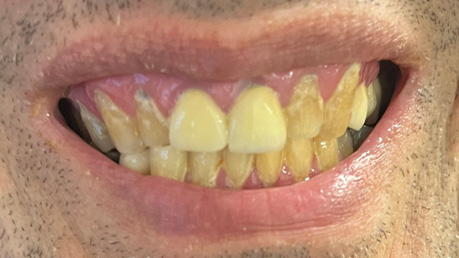

Patient Intraoral Photographs

- Frontal view

Dental Hygiene: The patient has osteoarthritis and cannot perform oral hygiene on himself. At the first appointment, he revealed he has a PSW that brushes for him using a manual toothbrush with Crest toothpaste 0.454% Stannous fluoride (1100 ppm fluoride) twice daily (morning before breakfast and before bedtime). No other fluoridated products are used at home. He consumes fluoridated tap water and does not use mouthwash. Fluoride varnish has been applied to his teeth at scaling and root planing (SRP) appointments. Currently, he has only been getting SRP once a year as a preventative procedure. His latest SRP was in October 2023 when I first saw the patient. During his last SRP appointment, there was heavy generalized plaque and supragingival calculus, moderate generalized subgingival calculus, and bleeding on probing (BOP) localized to the mandibular anterior teeth. The gingiva was red and inflamed throughout the mouth. The interproximal areas and gingival third of the teeth were often missed during his at-home oral hygiene regimen. The patient states the PSW brushes with horizontal strokes for less than 30 seconds each day. The patient states that he gets flossed every other day or every 3-4 days, but this did not correspond to what was seen clinically. He appeared motivated to attain better oral hygiene, but he states his PSW is not motivated to brush his teeth for longer durations and is reluctant to provide him with oral hygiene (OH) unless he requests for it daily. The patient has no family history of oral cancer, has never smoked, does not consume alcohol, does not use chewing tobacco, and does not excessively expose himself to the sun.

Carious Lesions: 12MV, 13DV, 14MOV, 25O, 31V, 42MV, 45V